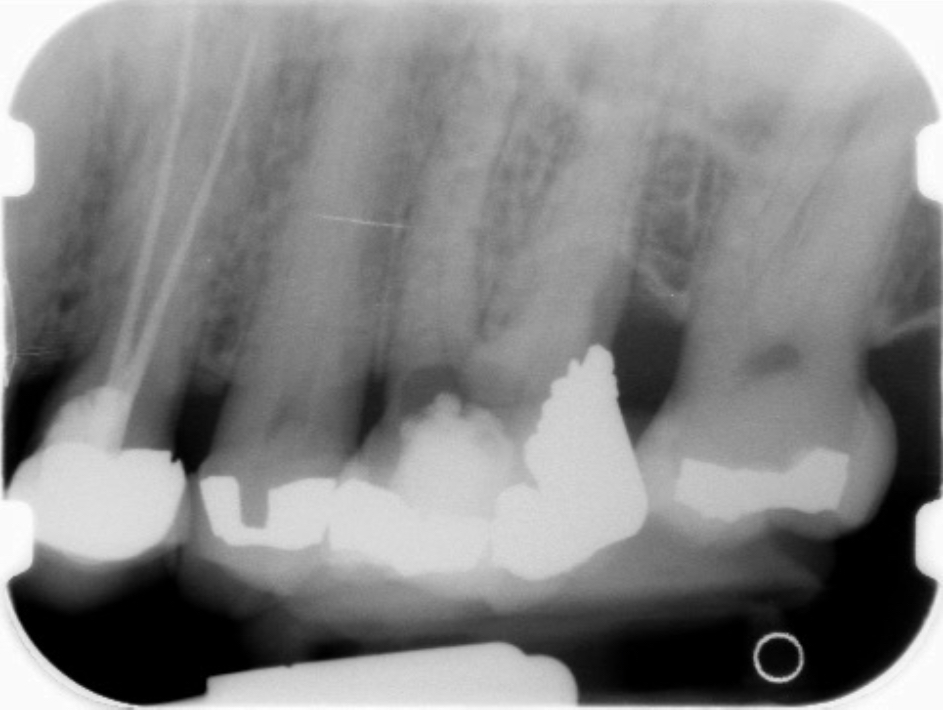

Perforations are generally the result of iatrogenic conditions in which a communication between the pulp canal and the periradicular tissue occurs during either access preparation or canal shaping procedures. Perforations can also happen in cases of internal root resorption, where the entire thickness of the root becomes affected by the resorptive process. Because of its excellent sealing ability and biocompatibility, MTA has been used to repair root perforations with predictable results.29,30

Clinical procedure: Once a perforation occurs, the extent of the perforation must be assessed. If there is an adjacent bony defect, the bony defect should first be filled with an osteoconductive or osteoinductive material. This can be done with a bone graft, calcium sulfate, or collagen/gelatin sponge. The dentinal portion of the tooth that has been perforated is then restored with MTA (Figure 9 through Figure 14).

Fig 9 Preoperative radiographs showing mesial perforation.

Figure 9

Fig 10. Preoperative radiographs showing mesial perforation.

Figure 10

Fig 11. MTA perforation repair done, and calcium hydroxide medication placed in the canals.

Figure 11

Fig 12. Postoperative radiograph.

Figure 12

Fig 13. 2-year follow-up radiographs showing the positive outcome.

Figure 13

Fig 14. 2-year follow-up radiographs showing the positive outcome.

Figure 14